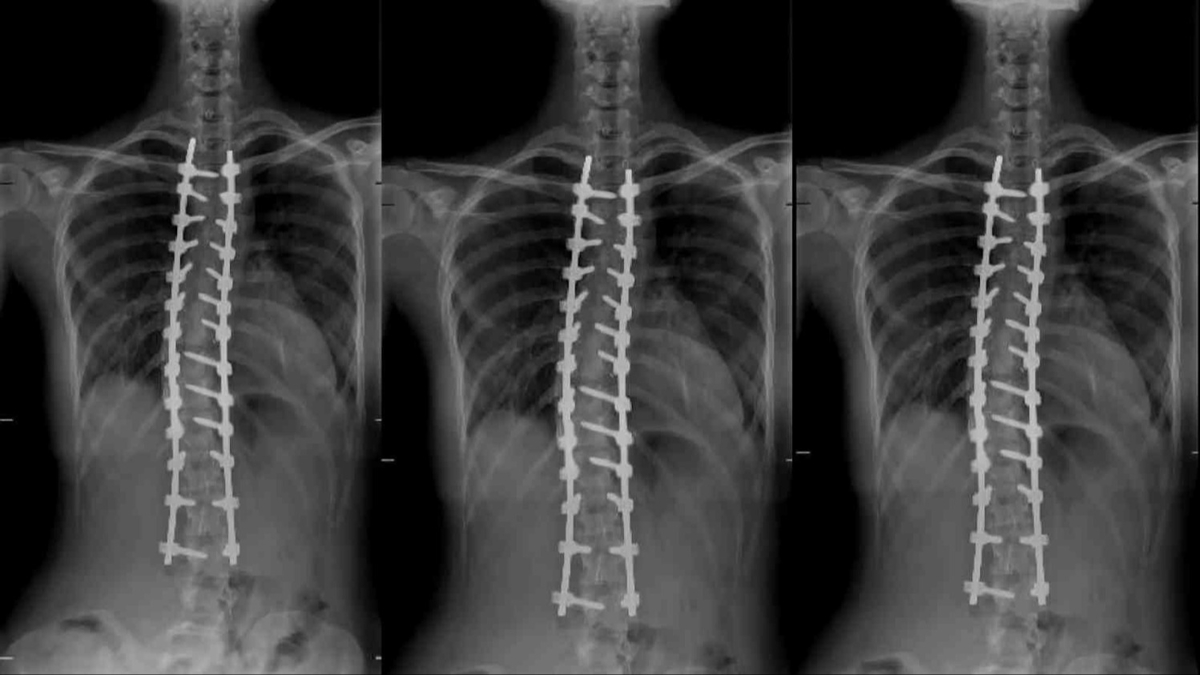

Omurga eğriliği ameliyatı risklerini en aza indirmek için ameliyatın yüksek hassasiyetle yapılmasını sağlayan modern teknolojiler ile skolyoz ameliyatlarının artık çok daha güvenilir hale geldiğini belirten Uysal, "Bu zamana kadar omurgada gerçekleşen ameliyatların beraberinde birtakım riskleri de getirmesinin birçok kişiyi düşündürmekteydi. Robotik skolyoz ameliyatı felç de dâhil olmak üzere birçok riski azaltıyor. Robotik omurga cerrahisi sayesinde omurgaya yerleştirilecek vidalarda yüzde 99,5 ve üzeri doğruluk oranının sağlanması, günümüzde skolyoz ameliyatlarından alınabilecek en iyi başarı oranını bizlere sunuyor" diye konuştu.

Son olarak robotik skolyoz cerrahisinin ameliyat sonrası süreçteki avantajına değinen Opr. Dr. Yunus Uysal "Hastaların meydana gelebilecek risklerden korkması doğaldır. Fakat robotik skolyoz cerrahisi sonrasında hastalar, geleneksel skolyoz ameliyatlarına göre daha az ağrı hissetmekte ve daha hızlı bir iyileşme sürecinden geçmektedir" dedi.